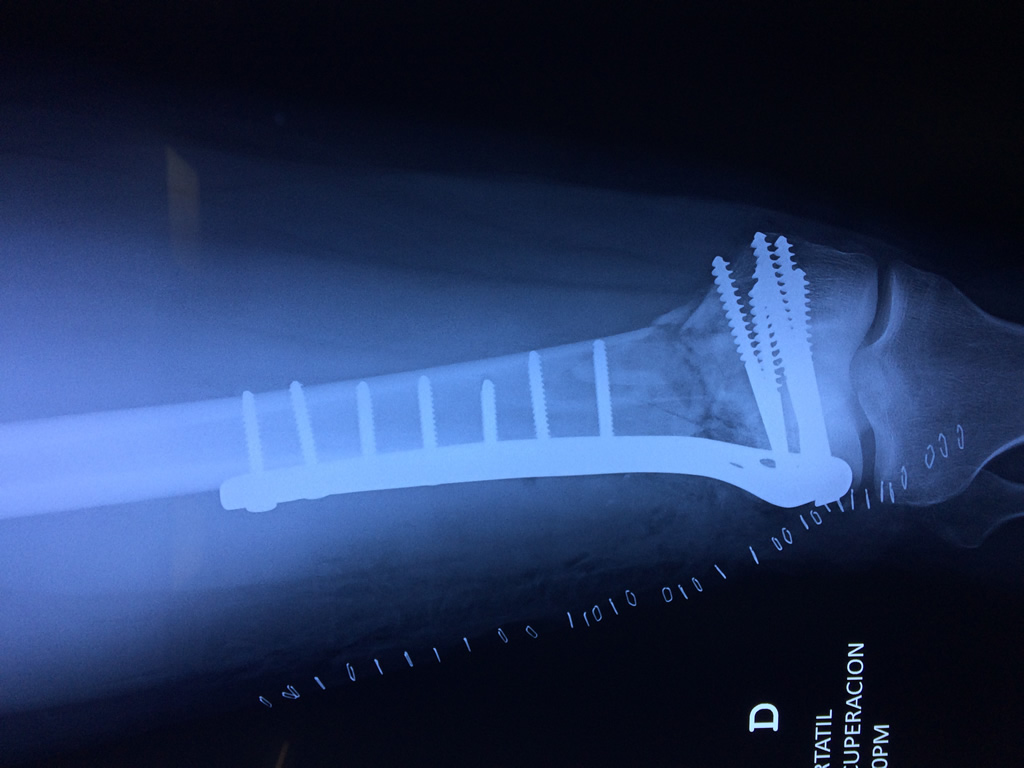

Cirugías de Rodillas

El fémur es el hueso del muslo, el segundo segmento del miembro inferior. Es el hueso más largo, fuerte y voluminoso del cuerpo humano.